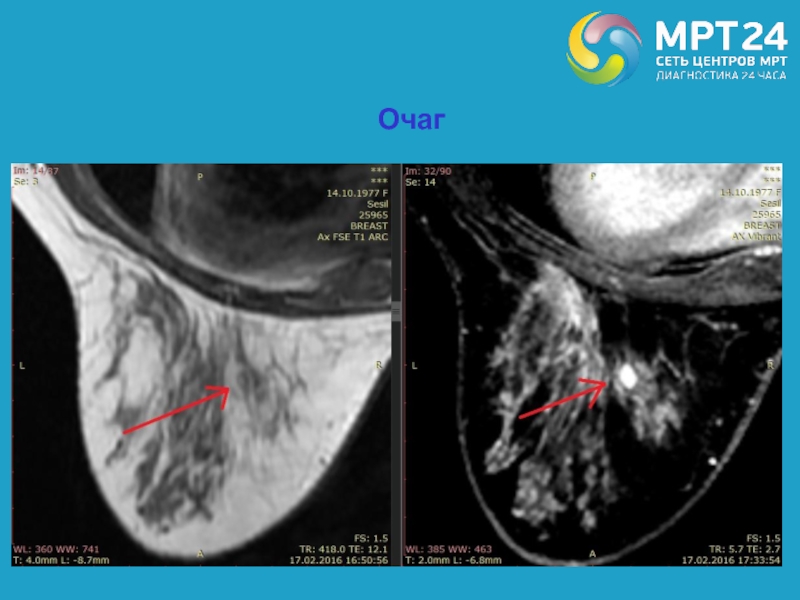

Слайд 33Выявляемые на МРТ в молочных железах контрастируемые структуры (стандартизированная терминология):

Очаг

(focus) – это маленький участок контрастного усиления (обычно менее 5 мм),

который ввиду небольшого размера сложно характеризовать и который не выявляется на доконтрастных изображениях.

Слайд 34Очаг